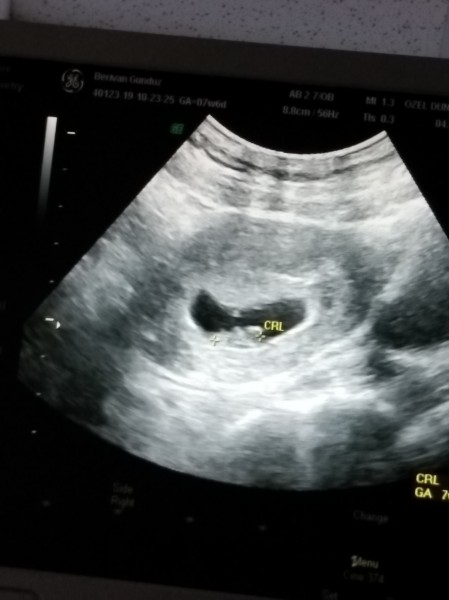

8 Haftalık Bebek Kalp atışı Yoksa

8 Haftalık Bebek Kalp atışı Yoksa.

yolk sac var bebek gorunmuyor hamilelik donemi genel